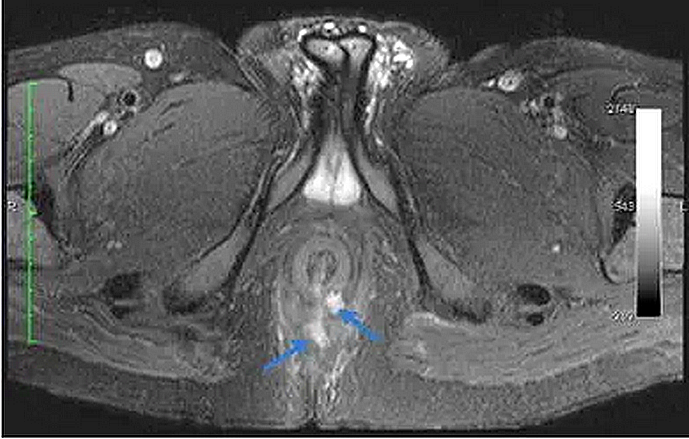

Chụp cộng hưởng từ rò hậu môn bao gồm hai giai đoạn trước tiêm thuốc và sau tiêm thuốc đối quang từ (tương phản từ). Mục đích chính của việc sử dụng thuốc đối quang từ là giúp hiện hình rõ đường rò và đánh giá mô xung quanh đường rò. Mặc dù phản ứng Dị ứng ít khi xảy ra với thuốc đối quang từ, bác sĩ sẽ hỏi bạn về tiền sử sử dụng thuốc cũng như tư vấn cho bạn lợi ích và nguy cơ của thuốc trong từng trường hợp cụ thể.

Một ca chụp cộng hưởng từ rò hậu môn khoảng 30-45 phút. Bạn sẽ nằm trên giường chụp và kỹ thuật viên sẽ đặt một thiết bị đặc biệt gọi là “Coil” quanh vùng bụng – chậu của bạn. Bàn chụp sẽ được đưa vào trong “lồng” và kỹ thuật viên sẽ bắt đầu lấy hình ảnh vùng chậu, bao gồm hậu môn và vùng xung quanh hậu môn. Bạn sẽ được kỹ thuật viên tiêm thuốc giữa quá trình chụp. Sau khi tiêm thuốc, đường rò hậu môn sẽ nổi rõ hơn trên hình ảnh, giúp bác sĩ nhận diện và đánh giá tổn thương tốt hơn.

Bác sĩ Chẩn đoán hình ảnh sẽ phân tích và đưa ra kết quả dựa trên hình chụp qua từng lát cắt mỏng vùng chậu. Qua đó, đường rò của bạn sẽ được phân loại dựa theo bảng phân loại hiện có. Đồng thời, nhu mô xung quanh đường rò sẽ được đánh giá và ghi nhận những bất thường đáng chú ý, trong đó có những biến chứng của đường rò (ví dụ nhiễm trùng, áp xe, đường rò tái phát...).